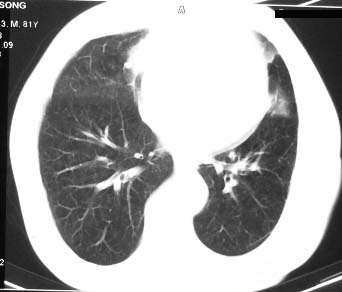

1左上叶周围型肺癌伴右上叶转移灶,右中叶转移灶可能性大,慢性炎症改变不除外2右上叶尖段陈旧结核灶3左侧胸膜轻度增厚.

右肺中叶软组织块,其周围可见多个类圆形结节,右肺上叶尖段见斑片、索条状致影,左肺小结节,见分叶、毛刺及胸膜凹陷征。1.左肺周围型肺癌伴右肺内转移; 2.右肺上叶陈旧性结核。

作者: yemin92007    时间: 2006-8-7 22:00

老年人,适用多元论,考虑 :1、左肺周围型肺癌伴右肺内转移; 2、右肺上叶陈旧性结核。